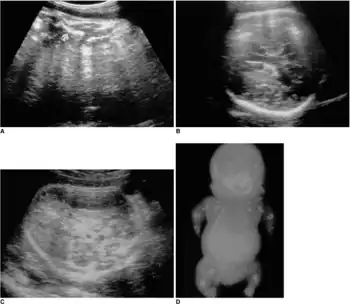

Achondrogenesis

Achondrogenesis is a number of disorders that are the most severe form of congenital chondrodysplasia (malformation of bones and cartilage). These conditions are characterized by a small body, short limbs, and other skeletal abnormalities. As a result of their serious health problems, infants with achondrogenesis are usually born prematurely, are stillborn, or die shortly after birth from respiratory failure. Some infants, however, have lived for a while with intensive medical support.

Researchers have described at least three forms of achondrogenesis, designated as Achondrogenesis type 1A, achondrogenesis type 1B and achondrogenesis type 2. These types are distinguished by their signs and symptoms, inheritance pattern, and genetic cause. Other types of achondrogenesis may exist, but they have not been characterized or their cause is unknown.